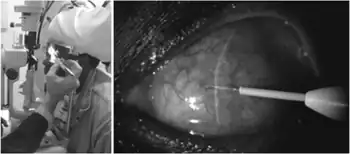

Subconjunctival injection

Subconjunctival injection is a type of periocular route of injection for ocular drug administration by administration of a medication either under the conjunctiva or underneath the conjunctiva lining the eyelid.

Using the subconjunctival injection bypasses the fatty layers of the bulbous conjunctiva and putting medications adjacent to sclera that is permeable to water, this will increase the penetration of the water-soluble drug into the eye.[1]